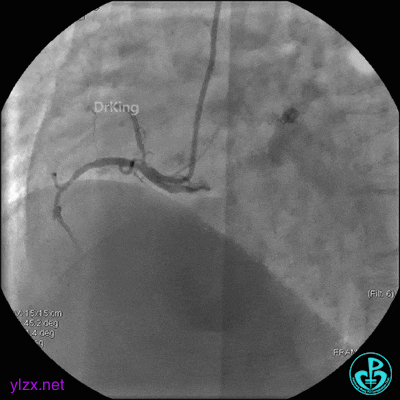

4 急诊冠脉造影

左主干轻度狭窄,左主干到前降支近端钙化影明显。前降支开口严重狭窄,近端闭塞。粗大回旋支轻度狭窄。

右冠脉无严重狭窄,右冠脉没有给前降支提供逆向供血。